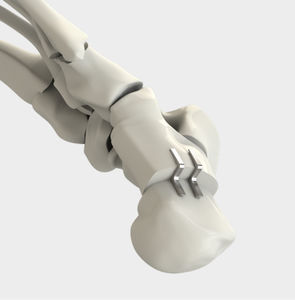

Orthopädische Klammern

... Volle Stabilität im Heftklammerhalter. Verstärkte Ecken für Stabilität. Wirksame Anti-Rückschlag-Verzahnung. Scharfe, abgeschrägte Spitzen. Für die Fixierung aller anatomischen oder prothetischen Komponenten. Für Knie- und andere Gelenke. Titan Die ...

... - ACL-PCL-MCL-LCL-Operation SPEZIFIKATIONEN - Innenliegende Spikes, geschärfte Zähne KRAFTKLAMMER TITAN 8X20 MM HEFTKLAMMER TITAN 10X20 MM HEFTKLAMMER TITAN 11X20 MM ...

U-Klammer aus Titan wird zur Fixierung des Weichgewebes am Knochen bei der ACL-Rekonstruktion verwendet.

Orthopädische Klammer / für Bandplastiken am Kniegelenk6062 series

... REF.NO LÄNGE (Mm) 6062-0006 6 6062-0008 8 6062-0010 10 6062-0012 12 ...

... Die Bandklammer wird zur Fixierung des Weichgewebes am Knochen bei der ACL- und PCL-Rekonstruktion verwendet. Es kann auch zur Fixierung von medialen und lateralen Bändern verwendet werden. ...

... für die Fixierung von medialen und lateralen Bändern. Hauptmerkmale: Verbesserte Lastverteilung: Die Orthosyn Titanium U-Klammer verfügt über eine breite Klammerbasis, die eine optimale Lastverteilung während des Einsetzens ...